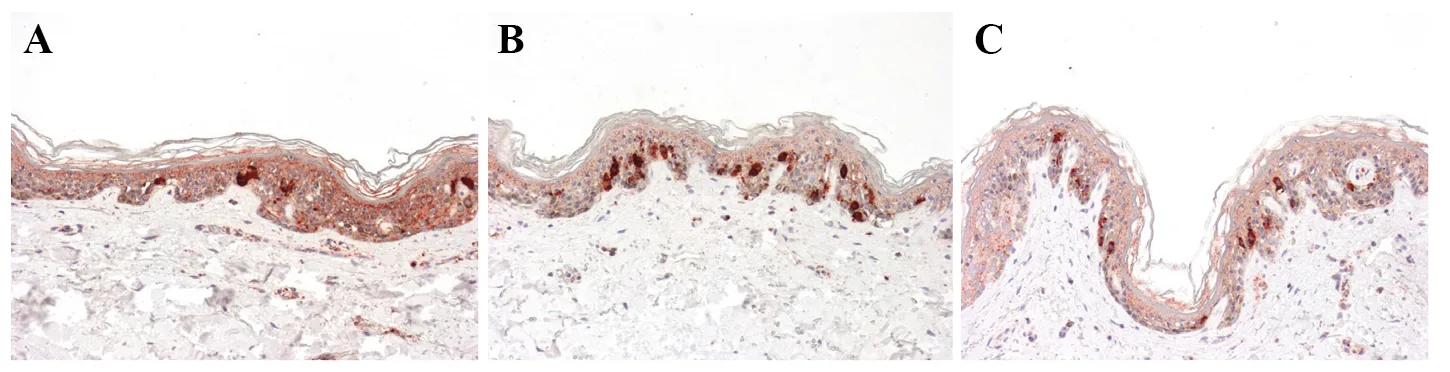

Evaluation of epidermal mitotic index

The immuno-detection observed just adjacent to the HE treatment zones on the whole slice (and not in the impact zone itself), revealed a very statistically significant augmen-tation of positive epithelial cells at D2. The percentage of mitotic cells rose from an average of 9.17% in experimen-tally aged skin to 15.52% in the skin exposed to low levels of radiofrequency (p = 0.002) and to 18.73% in the skin treated by HE high levels (p = 0.021).

The results are shown in table 1 and in figure 3. Increase in mitotic index is an indication of the natural wound healing process of re-epithelialization and the repair of damaged tissue in impact areas.

Figure 3. Immunohistochemical analysis of mitotic index at D2 (Ki67, ×200). A significant augmentation of positive epithelial cells is noticed in skin fragment B (UV+Low HE) and in fragment C (UV+High HE) in comparison to the control A (UV).